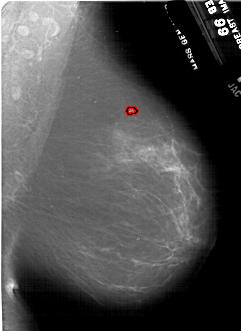

A_1848_1.LEFT_CC

LEFT_CC LINES 6766 PIXELS_PER_LINE 4531 BITS_PER_PIXEL 12 RESOLUTION 43.5 OVERLAY

FILE: A_1848_1.LEFT_CC.OVERLAY

TOTAL_ABNORMALITIES 1

ABNORMALITY 1

LESION_TYPE MASS SHAPE IRREGULAR MARGINS ILL_DEFINED

ASSESSMENT 4

SUBTLETY 4

PATHOLOGY MALIGNANT

TOTAL_OUTLINES 1

BOUNDARY